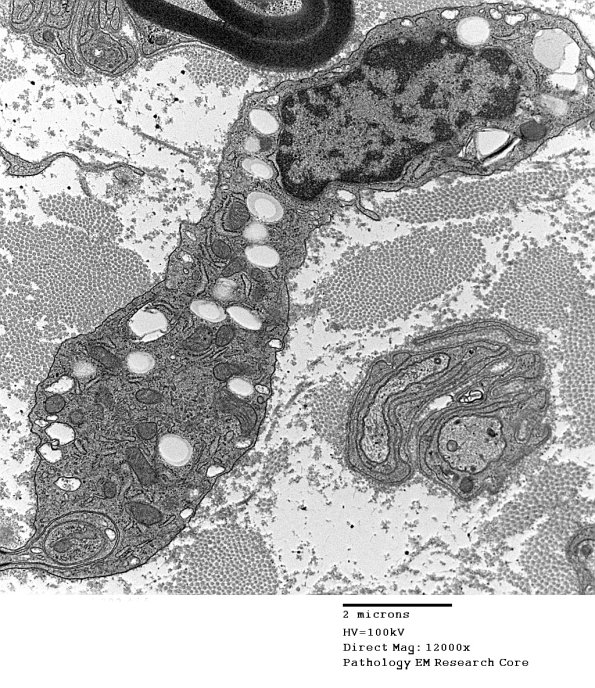

Washington University Experience | PERIPHERAL NEUROPATHY | 4 AXONAL DEGENERATION | 4 Macrophages | 4F2 (Case 16) EM 002 - Copy

A migrating macrophage with a small amount of debris.